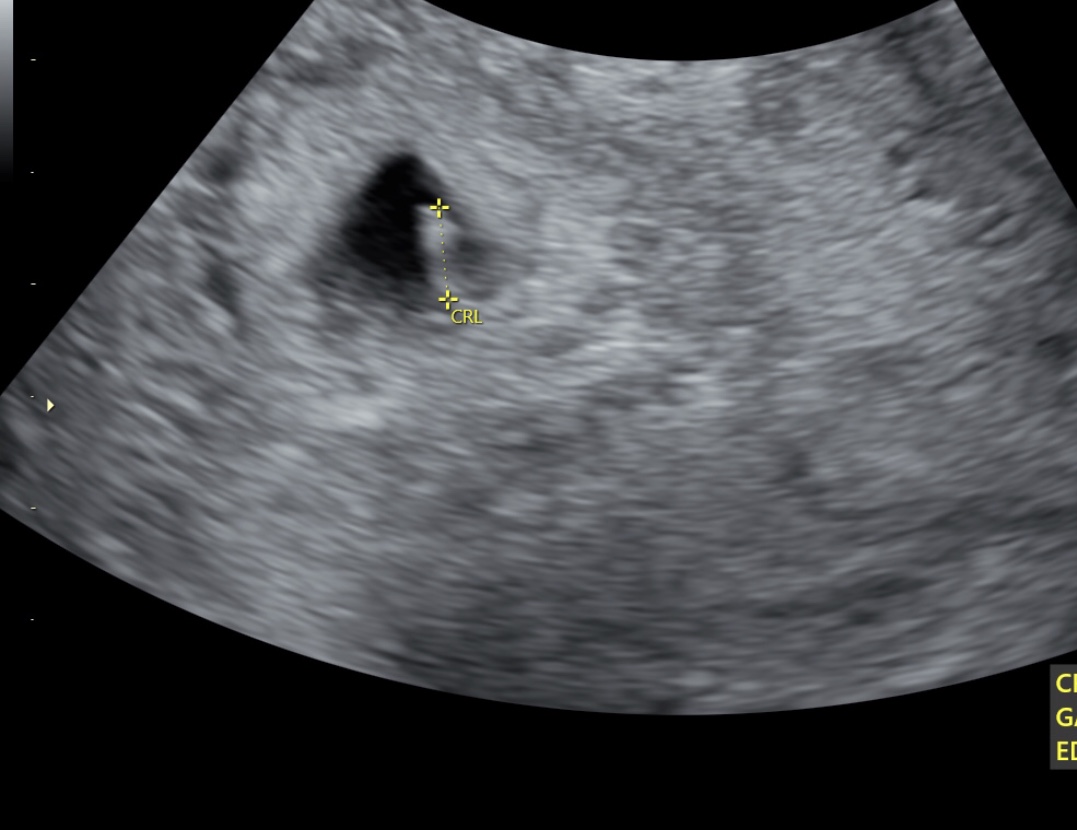

Hi ladies!! I’m baaaaaaack!! I finally got my BFP and now have a BFScan! Just for fun, would any of you gals mind having a Ramzi look for me?! Thanks in advance!Attachment 39662

Sorry, it’s transvaginal, 6 weeks